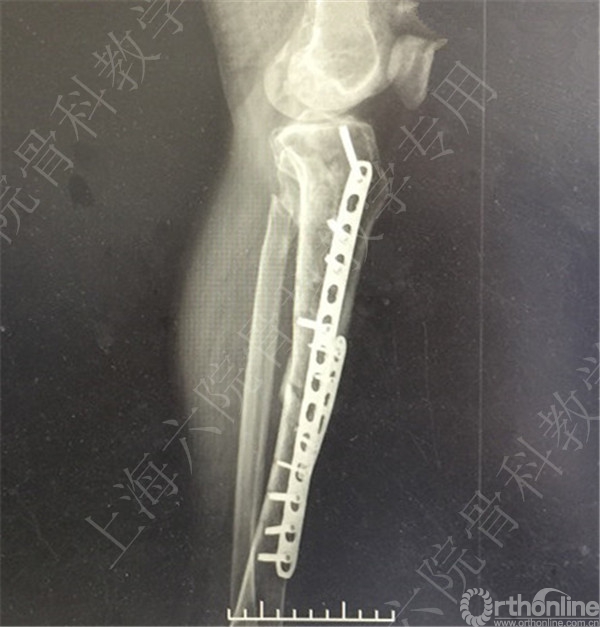

患者择期行左胫骨切开复位内固定术+髂骨异体骨植骨。

术后X线摄片示:骨折对位对线可,内固定牢靠,左胫骨对线可。

医方第一次跟换内固定术中,未纠正左胫骨立线,骨折对位对线差,未纠正成角,导致术后内固定失效,骨折成角变大。医方存在手术方式不当,手术操作不当,术后并发症观察、处理不当,对疾病评估不足,告知缺陷等过失。